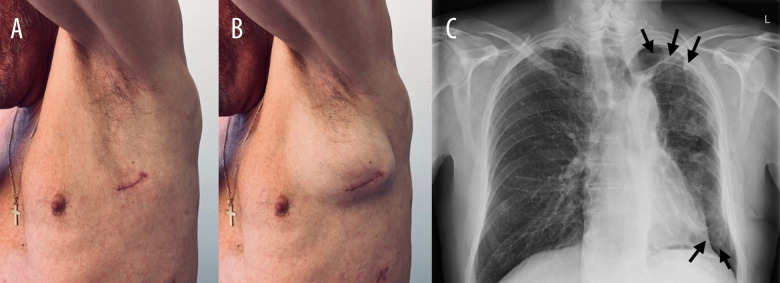

背景胸腔镜解剖肺切除术后,胸壁疝和残余胸膜间隙是已知的并发症。一些胸壁疝的危险因素已被描述;然而,残余胸膜间隙从未被描述为其中之一。我们报告的2例病例表明,术后残留的空气空间可能是胸壁疝的一个新发现的危险因素。病例报告:病例1:一名71岁男性在三孔胸腔镜下左下肺叶切除术治疗早期非小细胞肺癌1周后,在第4肋间切口处发生胸壁疝。他没有任何已知的术后胸壁疝的危险因素,但他的术后过程因残余胸膜间隙而复杂化。病例2:一名60岁男性,因早期非小细胞肺癌行三孔胸腔镜右根尖上叶节段切除术5个月后,在第四肋间切口术后出现胸壁疝。未发现术后胸壁疝的危险因素;然而,她的术后过程也因残余胸膜间隙而复杂化。结论胸膜残留气体通过胸腔镜切口可能阻碍伤口愈合,有利于胸壁疝的发生。在有风险的患者中采用视频辅助胸外科切口闭合技术可能有助于预防术后胸壁疝。这些病例强调了残留胸膜间隙可能是术后胸壁疝的一个新发现的危险因素,并提出了潜在的预防措施。

BACKGROUND Chest wall hernia and residual pleural space are known complications after thoracoscopic anatomical lung resection. Some risk factors for chest wall hernia have been described; however, residual pleural space has never been described as one of them. We present 2 cases suggesting that postoperative residual air space can represent a newly identified risk factor for chest wall hernia. CASE REPORT Case 1: A 71-year-old man developed a postoperative chest wall hernia at the fourth intercostal incision level 1 week after a 3-port thoracoscopic left lower lobectomy for early-stage non-small cell lung carcinoma. He was not known to have any described risk factors for postoperative chest wall hernia, but his postoperative course was complicated by a residual pleural space. Case 2: A 60-year-old man developed a postoperative chest wall hernia at the fourth intercostal incision level, diagnosed 5 months after a right apical upper lobe segmentectomy by 3-port thoracoscopy for early-stage non-small cell lung carcinoma. She was not known to have any risk factors for postoperative chest wall hernia; however, her postoperative course was also complicated by a residual pleural space. CONCLUSIONS We suggest that air flow through the thoracoscopic incision, due to residual pleural air, could impede wound healing and favor chest wall hernia. Adaptation of the closure technique for video-assisted thoracic surgery incisions in patients at risk may help prevent postoperative chest wall hernias. These cases highlight the possibility that residual pleural space could be a newly identified risk factor for postoperative chest wall hernia and propose potential preventive measures.